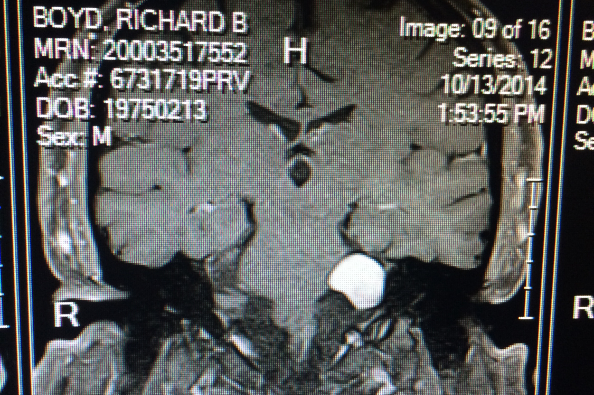

Also, my husband is having brain surgery on May 11 due to an Acoustic Neuroma brain tumor. It is lethal if untreated and has been causing hearing loss, headaches, facial numbness, and swallowing problems. His surgery is at Stanford in California, and we can't afford travel expenses to get him there and back.